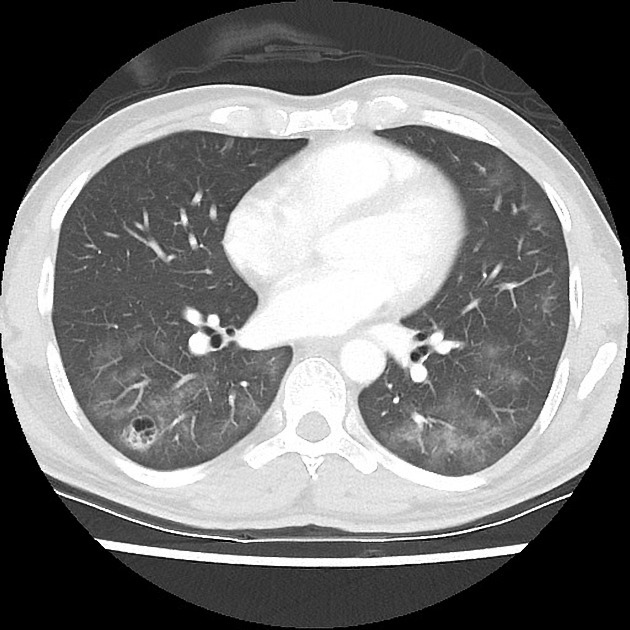

HOMEM, 35 ANOS, TOSSE CRÔNICA

PROTEINOSE ALVEOLAR